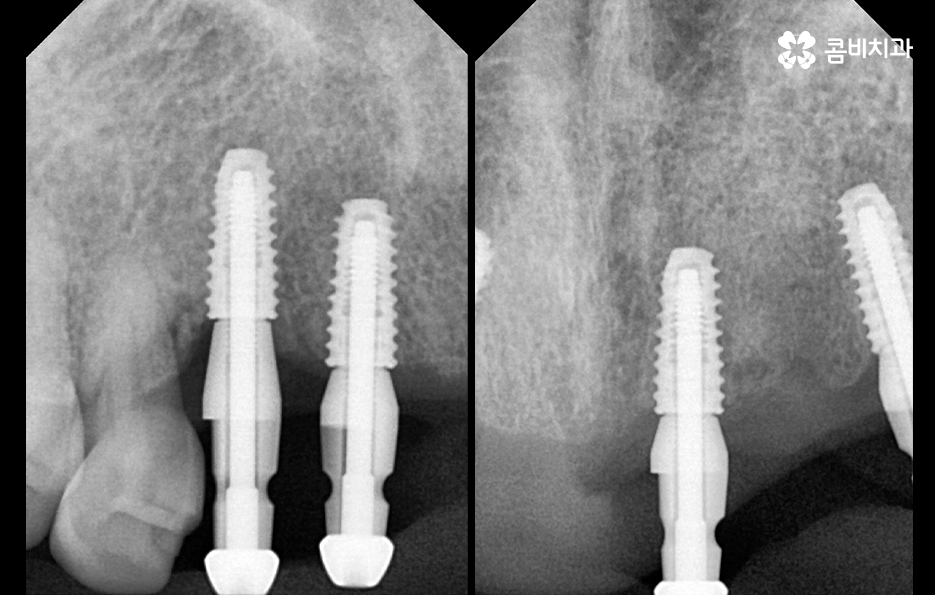

임플란트 치료는 되도록 치아를 상실한 개수와 1:1로 비례하여 식립하는 것을 권장하고 있는데 그 이유는 치아의 저작력에 있어서 우리의 모든 치아를 각각의 역할과 기능이 있고 압력에 대한 분산 효과도 있는데요

치아를 잃은 개수보다 적게 임플란트를 식립하게 될 경우 그만큼 저작력도 약해지고 임플란트에 가중되는 압력과 부담이 더 커질 수 밖에 없을 거예요. 자연치아와 임플란트의 가장 큰 차이점은 치주인대의 유무인데 치주인대 또한 음식을 씹을 때 얻는 압력을 분산하고 완화시키는 역할을 하고 있어요

임플란트는 치주인대가 없기 때문에 아무리 단단하게 잇몸 뼈에 고정되어 있어도 자연치아에 비해 저작기능에 의한 부담을 더 크게 받을 수 밖에 없는 거예요.

임플란트의 기본 원리가 잇몸 뼈에 임플란트를 식립하여 골유착을 통해 저작력을 얻게 되는데 임플란트의 수명 관리에는 주기적인 검진과 스케일링을 통한 임플란트와 잇몸 관리의 중요성이 큰 만큼 정품 재료의 선택 및 오랫동안 믿고 찾을 치과를 선택하시길 바라고 있어요